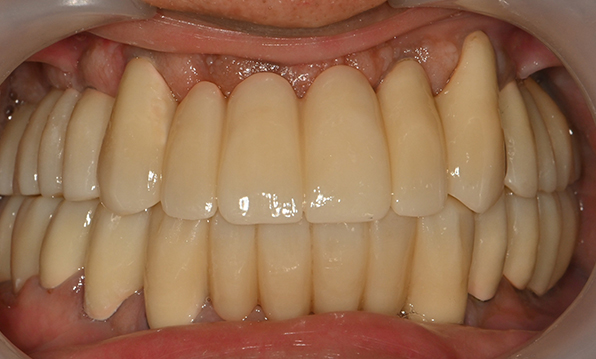

위 아래 치아가 정확하게 맞아야하는 고난이도 임플란트

임상 경험이 많은 숙련된 전문의의 섬세한 기술력이 중요합니다.

치료기간 : 2021.04.12~2021.09.15